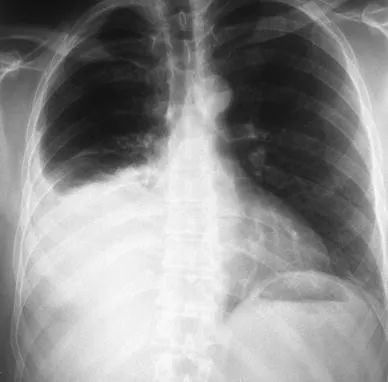

(3)延遲出血

延遲出血的其他原因是動靜脈瘻和動脈假性動脈瘤(圖 1)。這些併發症很少見,佔所有病例的 1.2% 。患者通常在經歷一個複雜多事的過程後出院,並在幾天甚至幾周後返回,抱怨持續性輕度血尿。該病的特徵是間歇性或持續性血尿、血紅蛋白緩慢下降,很少出現低血壓或肉眼血尿。腹部 CT 可證實診斷,應透過選擇性栓塞術進行治療 。

![]()

圖1 透過栓塞治療,右腎假性動脈瘤導致延遲出血和腎周血腫形成。a, b 栓塞前。c、d 栓塞後

包膜下腎或腎周血腫是非常罕見的出血併發症。它們大多是由於其他原因(例如,腎絞痛)在放射學評估後被意外診斷出來的,並且通常會順利消退 。CT 掃描也是區分血腫和尿腫的建議檢查。保守治療在大多數情況下是有效的,而很少需要介入措施(或放置經皮引流)。